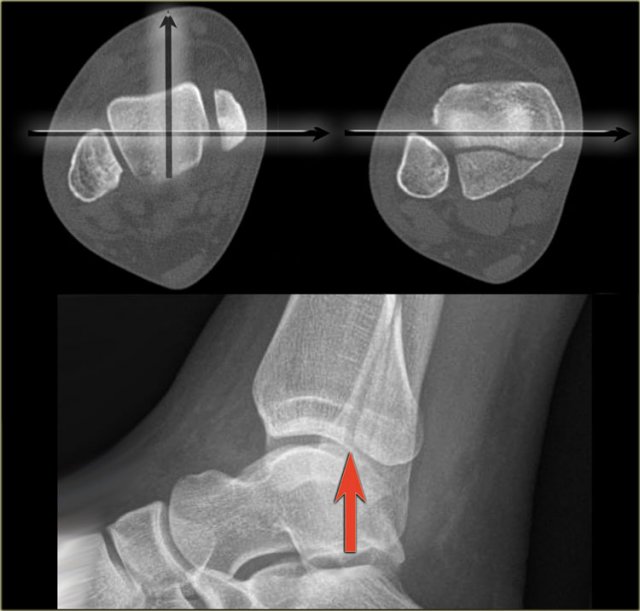

The CT demonstrates a large tertius fracture.

On the lateral view and also on the AP- and Mortise views, which will be shown in the paragraph on tertius fractures, this fracture was not visible.

The explanation is that on the lateral radiograph the fibula projects in the middle of the tibia.

The x-ray beam is not parallel to the fracture line.

Since the fracture line of a tertius fracture always has this orientation, we must insist on a true lateral view.

Good positioning of the lateral view - Tertius fracture Good positioning of the lateral view - Tertius fracture

On a well positioned lateral view the tertius fracture is obvious (red arrow).

This was the only fracture that was seen on the x-rays of the ankle and this patient turned out to have an unstable Weber-C fracture and went for surgery.

The x-ray beam has to be centered on the malleoli.

Notice the exorotation of the foot for a proper lateral view.